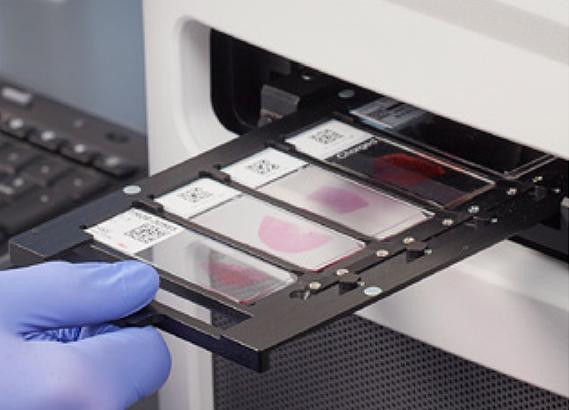

The Leica Biosystems Advantage: Designed for Digital Readiness

Snowcoat Slides |

Our expertise in pathology workflows enables us to deliver integrated solutions - including digital-ready glass coverslips - that streamline operations today and position laboratories for a digital, AI-powered future.